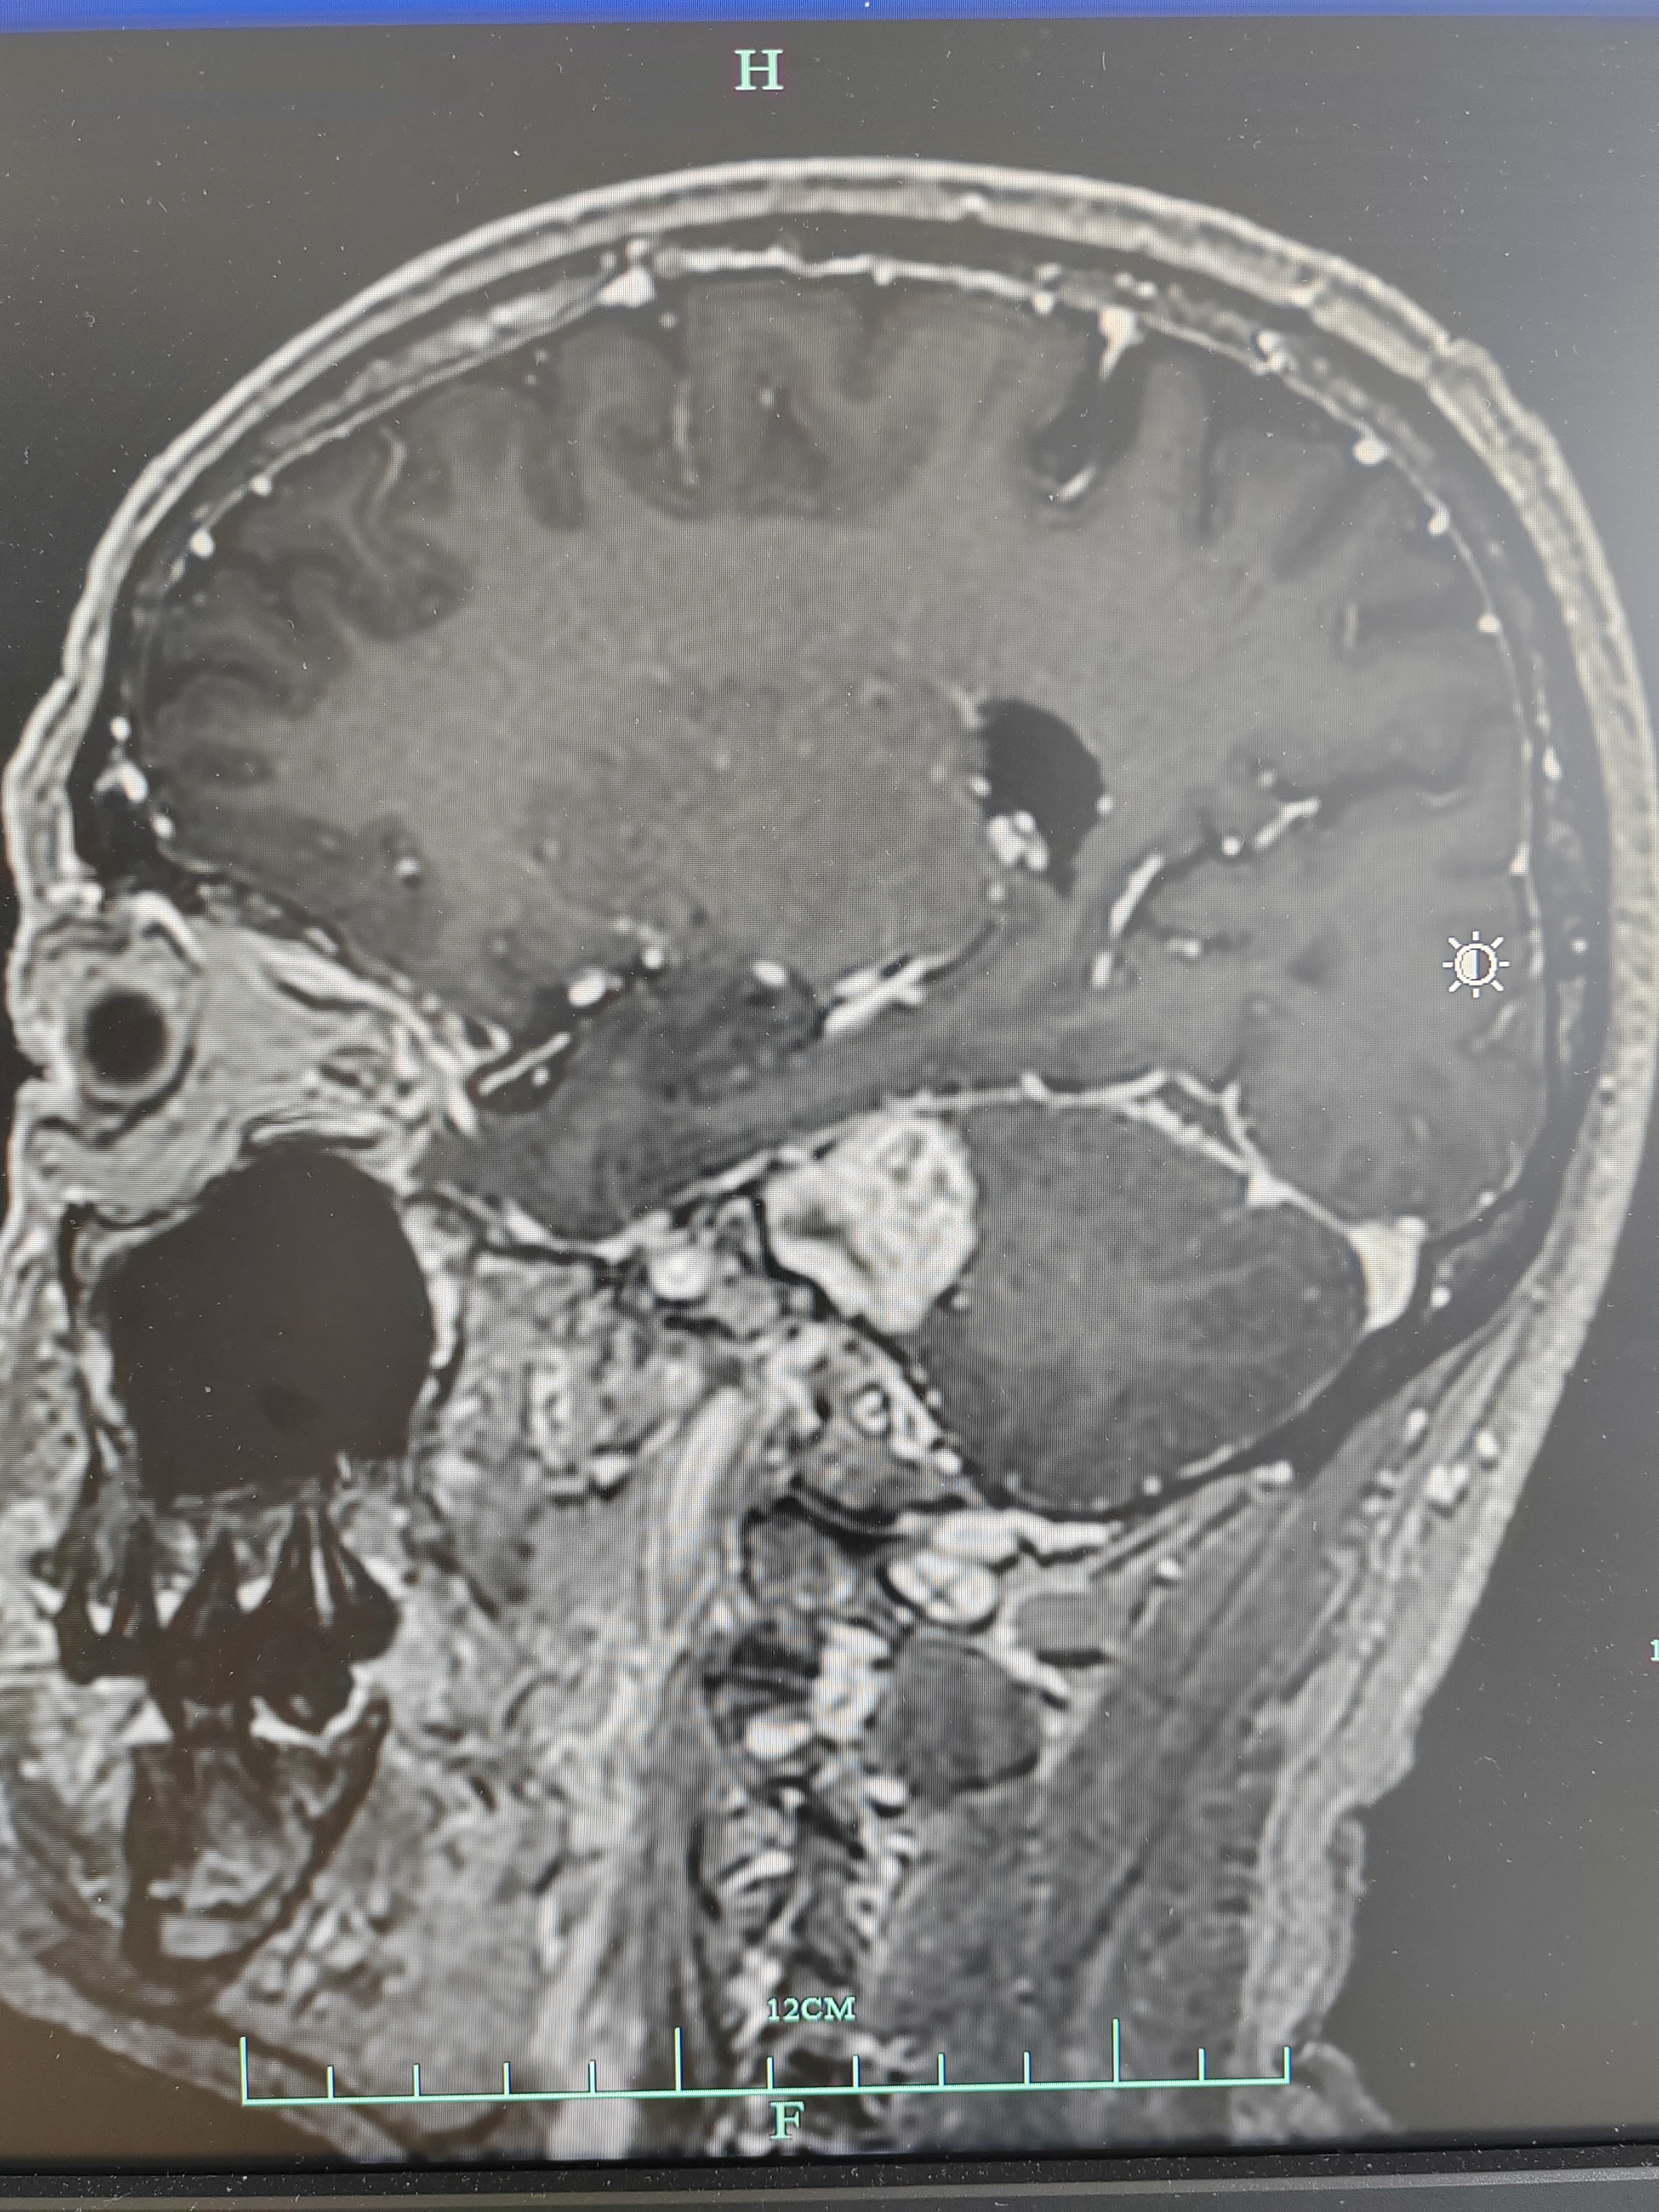

术后磁共振增强复查提示肿瘤全切,内听道内肿瘤无残留

内听道内高信号影为填塞的脂肪块